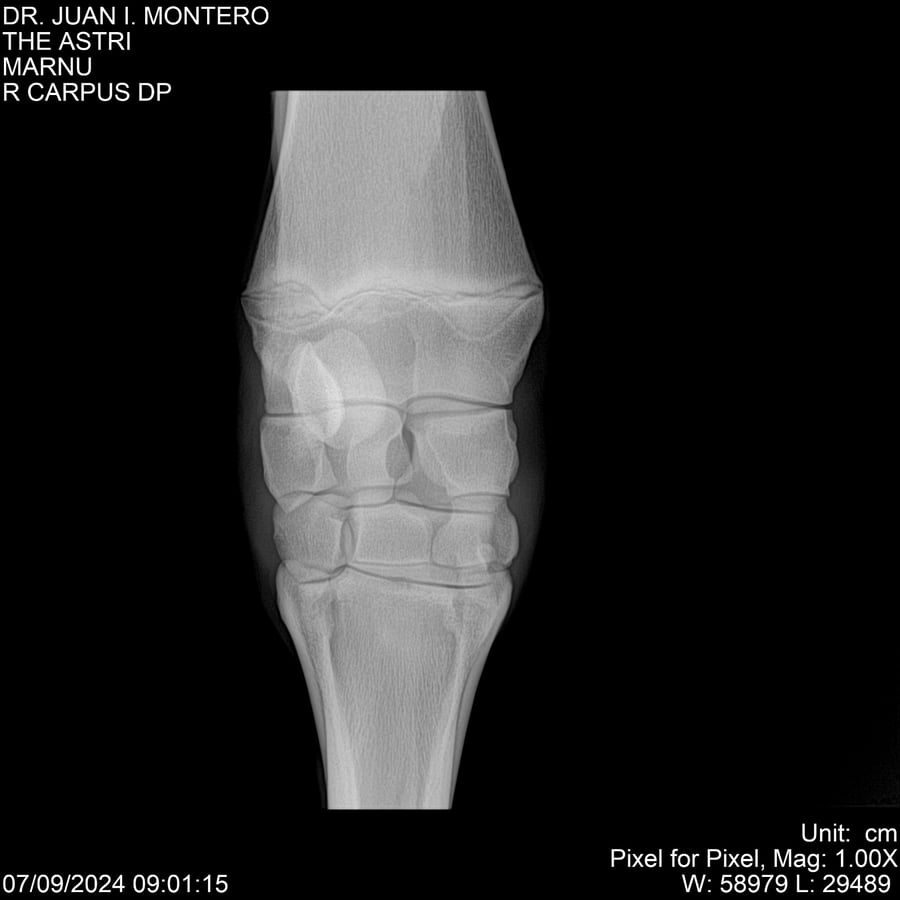

LOTE 10, THE ASTRI Lote Anterior Volver al remate Lote Siguiente Ficha Contacto Montevideo - Ficha del Lote Identificador: #282514 Categoría: Yeguarizos Montevideo - 60 Visualizaciones ClicData Contacto Empresa: Abelenda N. R., Walter Hugo Nombre*: Teléfono* : E-mail* : Mensaje Enviar Registrese gratis Este contenido Exclusivo está disponible sólo para usuarios registrados Ingresar